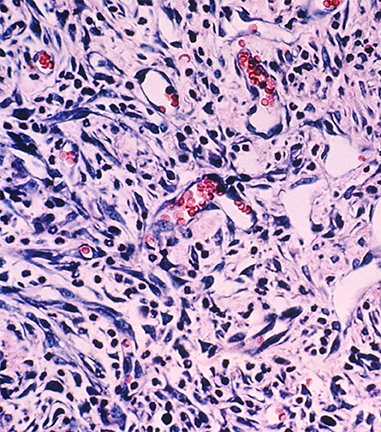

LSU Health faculty have developed new drugs that are showing early promise in selectively and effectively attacking cancer cells while leaving healthy cells alone. In an ongoing clinical trial for patients with KS, approximately 80% of patients have responded to a new medication designed to concentrate preferentially in KS tumors and, therefore, reduce side effects for the patient. Thus far, the drug appears to be both safer and more effective than standard medications for KS.